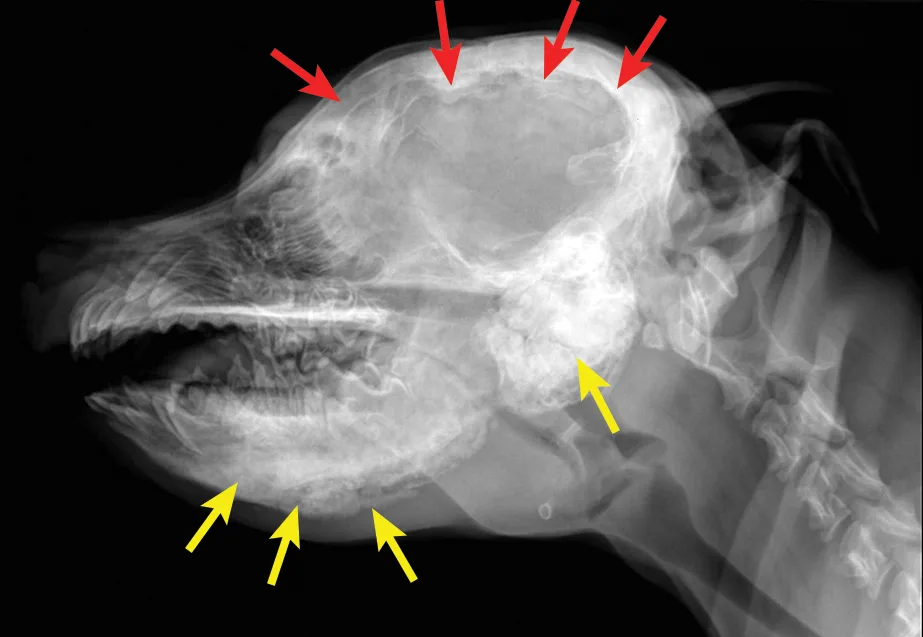

Diagnosis is based on signalment, history, clinical signs, and radiographic findings. Although biopsy and histopathology can help confirm diagnosis, they are typically not necessary, as radiographic findings are often pathognomonic (Figure 1). However, although standard radiographs can confirm diagnosis, CT may be helpful in assessing if the temporomandibular joints are affected.

(A) Lateral and (B) ventrodorsal radiographs of the skull. This patient was diagnosed with calvarial hyperostosis. Note that the frontal, parietal, and occipital bones, including the tentorium osseum, are smooth but have increased thickness and opacity (red arrows). Note the markedly irregular periosteal reactions on the mandibles and bullae (yellow arrows). This patient was unable to open its mouth much beyond what is evident on the lateral image. Images courtesy of Justin Goggin, DVM, DACVR